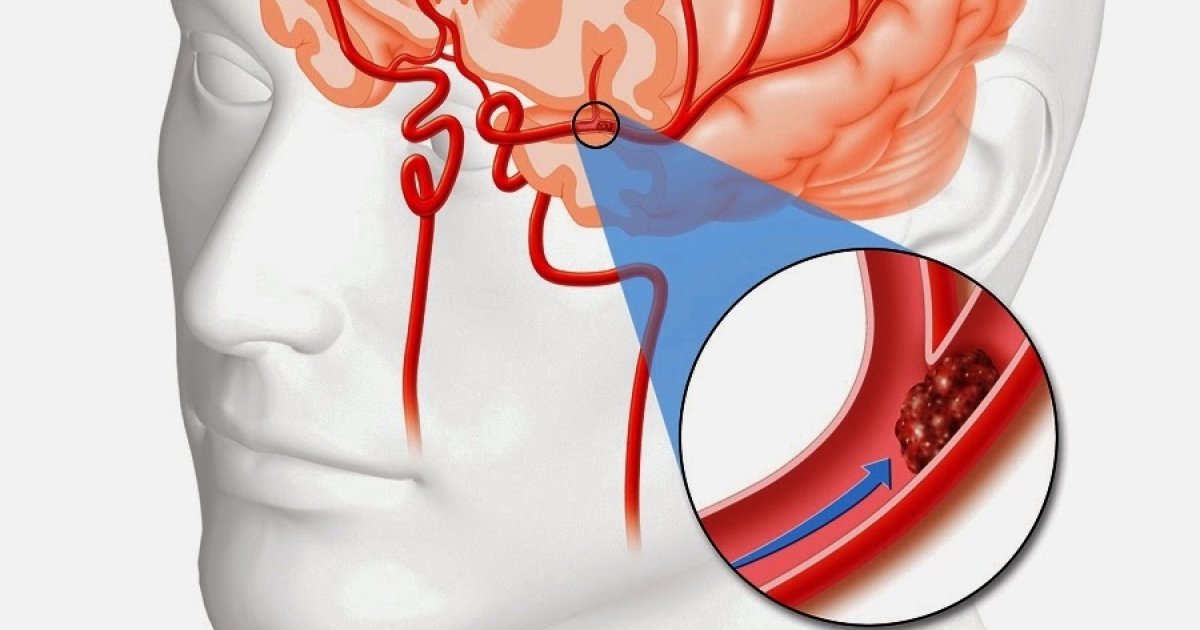

бральная эмболия

Церебральная эмболия 111 фотографий